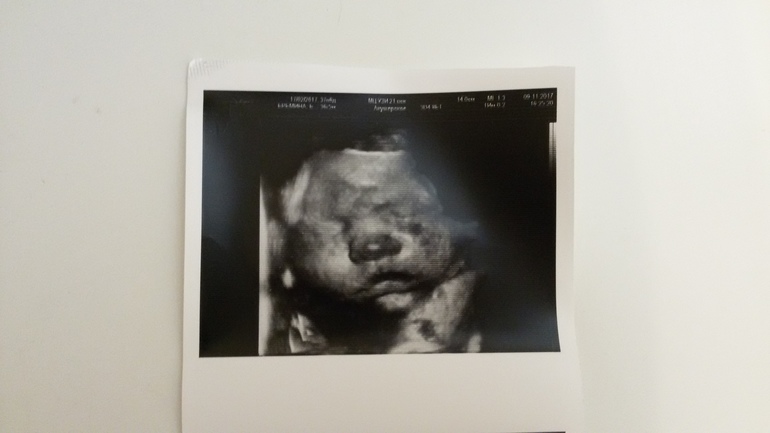

Завтра наш кружок замкнется) Сегодня ездили на узи посмотреть,как себя чувствует сынок,и вот наши новости)Плацента у нас еще не созрела ,щеки еще наедаем надежда родить пораньше отпала, недели две еще прохожу,весит уже 3467гр.,приблизительно сказала ,что рожу на 3800,ну вроде не совсем большой уверена,что справлюсь😉я буду очень стараться,сынок я тебе это обещаю☺что еще из хорошего мы без бус это очень радует,воды нормально,все соответствует сроку

вроде со всем определилась, осталось мелочь в сумку в рд докупить,а так все настирано и наглажено))) Уже дома я поняла, что рожу маленькую копию четвертой дочки вот посмотрите ,как они похожи